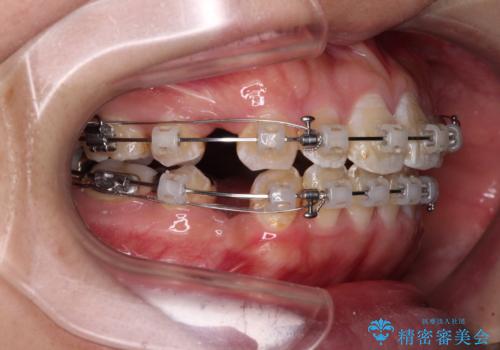

- クリアブラケット

- 2年2ヶ月

- 10-30回

むし歯のリスクが高かったため、治療が長期化しないように心がけました。

当初の予定通り、2年強で無事に治療を終えることができました。